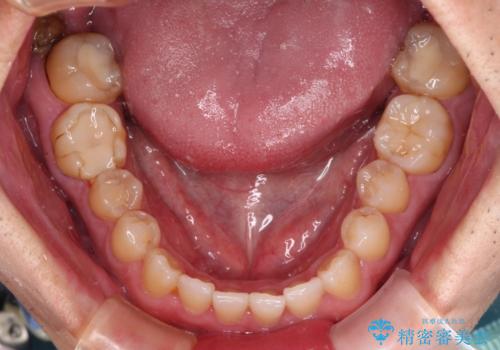

長期海外赴任が近いとのことで、出発に間に合うようにアポイントを調整して治療を進めて行きました。

中途半端に歯冠の見えている親知らずもあったため、そちらも出発前に抜歯を行いました。